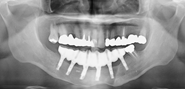

下顎骨の腫瘍で下顎を切除し(写真左)、切除したところを腰骨で再建し(写真中央)、インプラントを支えにしたブリッジ(写真右、白い部分)でかめるようにした症例のエックス線写真